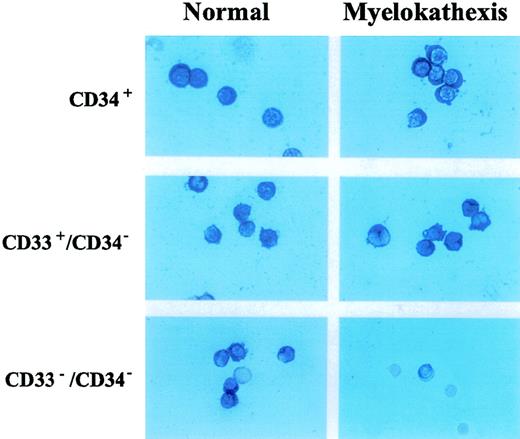

Neutrophils appear to be committed to apoptotic death in vitro and in vivo.17,26 This fate may result, at least in part, from constitutive coexpression of Fas and Fas ligand in neutrophils.17,23 26 Therefore, we examined and compared the expression of pro-apoptotic factors (ie, Fas and Fas ligand) and anti-apoptotic factors (ie, bcl-x and bcl-2) in bone marrow-derived cell populations from patient 2 and a healthy volunteer. Flow cytometry analysis revealed no difference in expression of either Fas or Fas ligand on CD37+, CD33+/CD34−, and CD15+/CD34−/CD33− cell populations from patient 2 when compared with corresponding cell populations from the healthy volunteer (data not shown). Immunocytochemical analysis revealed the equivalent expression ofbcl-2 in these cells (data not shown). Expression ofbcl-x, however, was strongly and selectively decreased in the CD15+/CD34−/CD33− cell population of patient 2 when compared with that of the healthy volunteer (Figure 5). A similar decrease inbcl-x expression was also observed in the corresponding cell population from patient 3 (data not shown). These data suggest that the depressed expression of bcl-x may contribute to increased apoptosis of neutrophil precursors in the bone marrow of patients with myelokathexis.

Immunocytochemical detection of bcl-x expression in CD34+, D33+/CD34−, CD34−/CD33− hematopoietic subpopulations purified from bone marrow of patient 2 and a healthy volunteer.

Immunocytochemical detection of bcl-x expression in CD34+, D33+/CD34−, CD34−/CD33− hematopoietic subpopulations purified from bone marrow of patient 2 and a healthy volunteer.

Effect of G-CSF treatment

Recombinant human G-CSF treatment resulted in significant increases in peripheral blood neutrophil counts (Table2). Using immunocytochemistry, the level ofbcl-x expression in the bone marrow-derived CD15+/CD34−/CD33− cell population from patient 2 during G-CSF therapy was examined. Bcl-xexpression was scant or absent before G-CSF treatment (Figure6). However, in response to G-CSF treatment, bcl-x expression increased significantly to a level comparable to that observed in CD15+/CD34−/CD33− cells from the healthy person (Figure 6).

Immunocytochemical detection of bcl-x expression in bone marrow-derived neutrophil precursor CD15+/CD34−/CD33− cells of a normal volunteer and patient 2 before and during treatment with G-CSF.

Immunocytochemical detection of bcl-x expression in bone marrow-derived neutrophil precursor CD15+/CD34−/CD33− cells of a normal volunteer and patient 2 before and during treatment with G-CSF.

Accelerated apoptosis of bone marrow progenitor populations has been implicated in the pathogenesis of cytopenias associated with myelodysplastic syndromes.46,47 It has been shown that the ratio of pro-apoptotic and anti-apoptotic factors may determine the survival capacity of a particular cell or tissue.18 19Therefore, the bone marrow-derived myeloid cells of neutrophil lineage (CD34+, CD33+/CD34−, and CD15+/CD34−/CD33− cell subpopulations), separated according to the expression of cell surface antigens, were analyzed by flow cytometry and immunohistochemical staining for the expression profile of Fas, FasL, bcl-2, andbcl-x, all of which have been implicated in the regulation of apoptosis of hematopoietic cells. These studies revealed impaired expression of bcl-x in the bone marrow-derived CD15+/CD34−/CD33− cell population in myelokathexis (Figure 5). The expression levels of Fas, FasL, and bcl-2 in myelokathexis did not differ from respective control cell populations. These data indicate that the expression ofbcl-x is abnormally depressed in bone marrow-derived granulocyte precursor cells from patients with myelokathexis. The resultant disturbed balance in pro-apoptotic and anti-apoptotic factors may then drive accelerated apoptosis of the myeloid precursor cell population.

During G-CSF therapy for bcl-x, immunohistochemical staining of bone marrow-derived CD34−/CD33−cells from a patient with myelokathexis demonstrated an increased number of cells positive for bcl-x expression (Figure 6). These data strongly suggest that G-CSF therapy resulted in an upregulation ofbcl-x gene expression, which is impaired in patients with myelokathexis. Furthermore, these observations implicate an important role for bcl-x expression in the regulation of cell survival during myeloid development, consistent with previous findings inbcl-x knockout mice.34